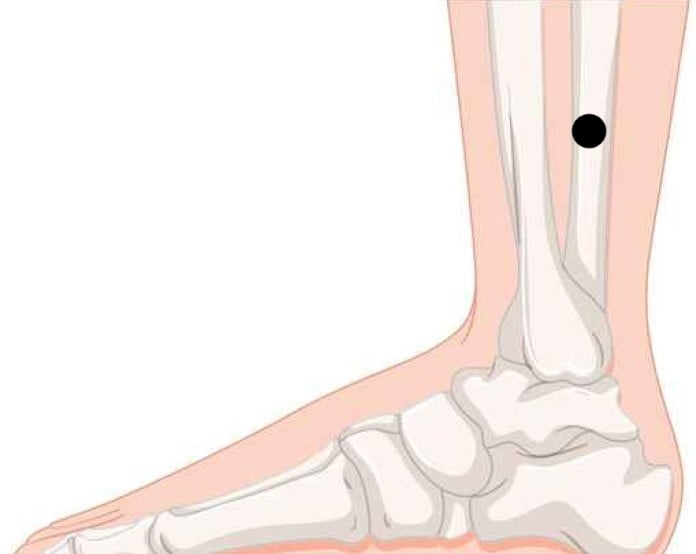

2. Sanyinjiao

Sanyinjiao, ook wel bekend als Milt 6 (SP6), is een belangrijk acupunctuurpunt voor gewichtsverlies. Het bevindt zich langs de miltmeridiaan, iets boven het binnenste enkelbot. Volgens TCM beinvloedt Sanyinjiao de organen van de onderbuik en het parasympathische zenuwstelsel. Door de spijsvertering, het metabolisme en urinaire en gynaecologische functies te bevorderen, kan acupunctuur bij SP6 tevens een persoon helpen gewicht te verliezen.